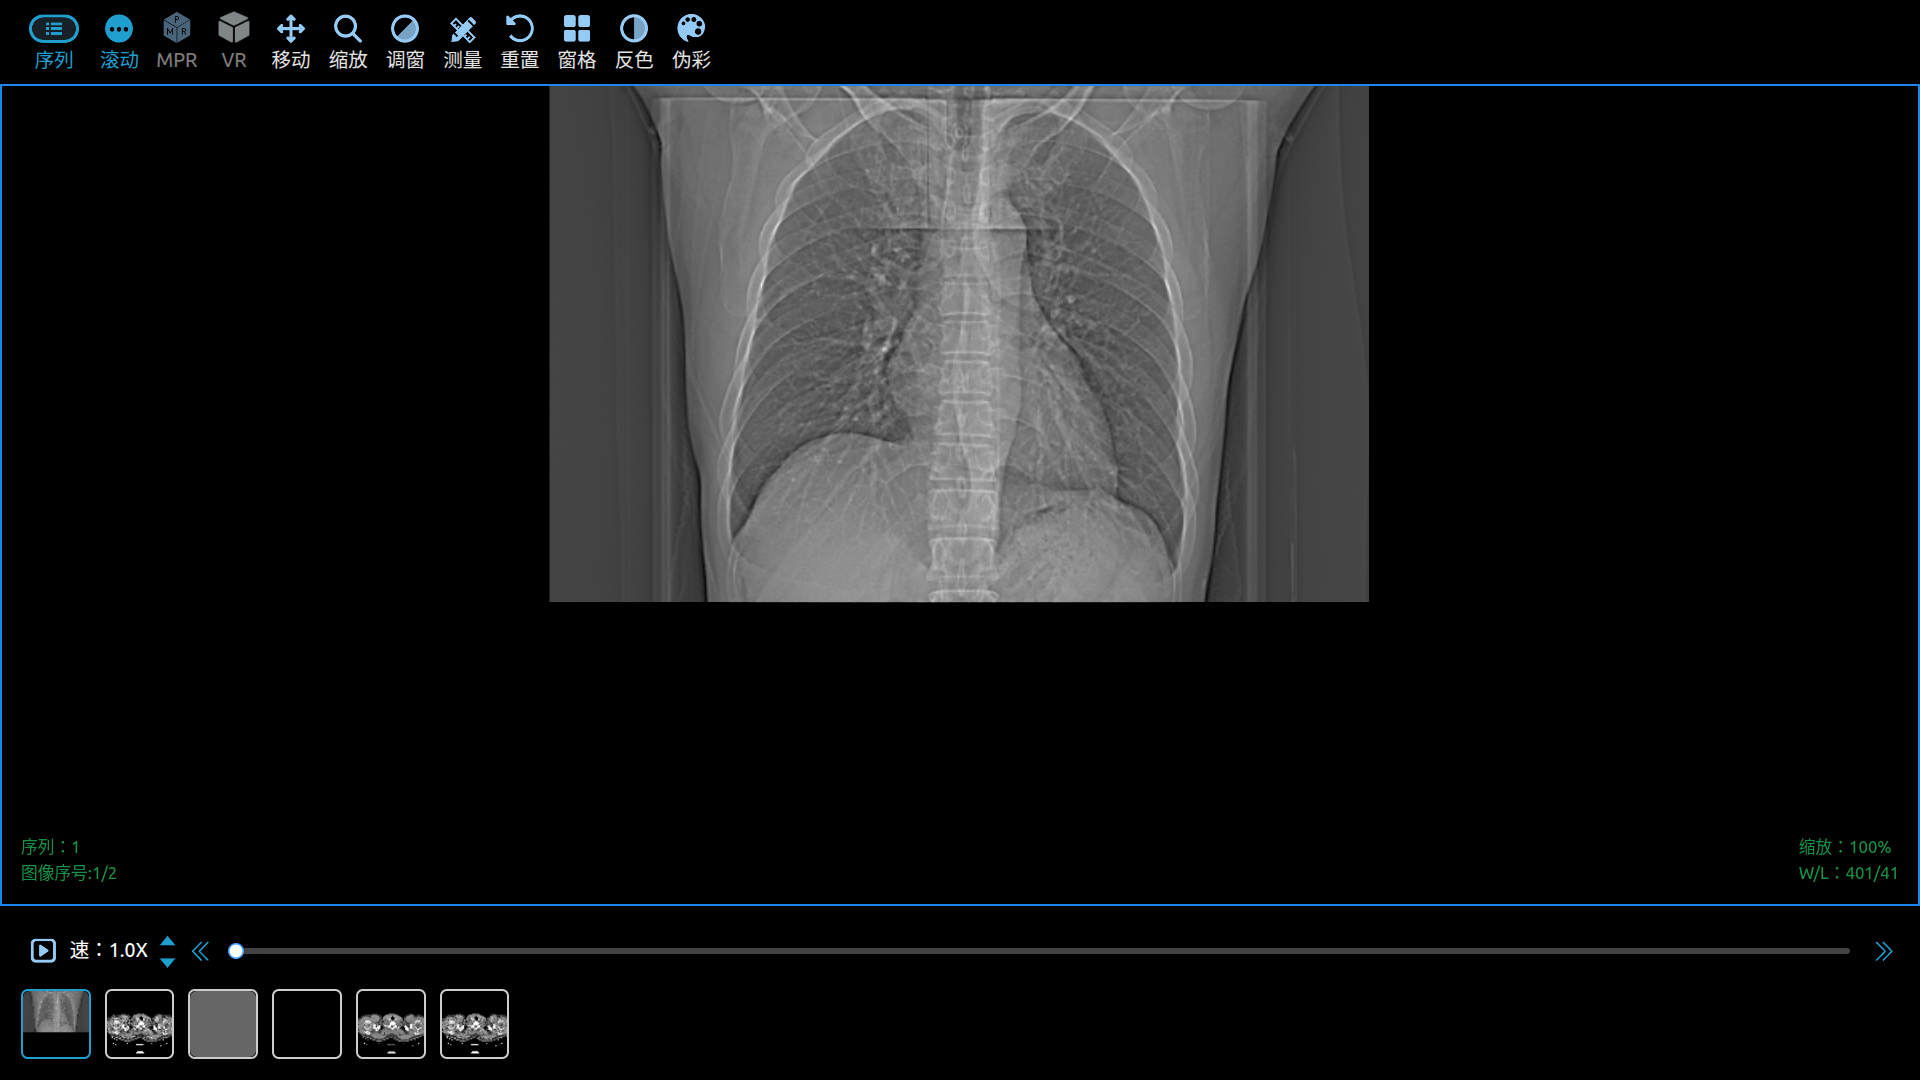

Use Cornerstone3D to View DICOM Images in a Web Browser.